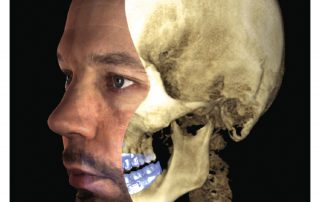

Planmeca ProMax 3D is a product family consisting of exceptional all-in-one units. All Planmeca CBCT units support three different types of 3D dental imaging – as well as panoramic, extraoral bitewing and cephalometric imaging. Planmeca is the first company to combine three different types of 3D data within one X-ray unit, ensuring these intelligent machines meet all maxillofacial imaging requirements. The ProMax family brings together a Cone Beam Computed Tomography (CBCT) image, 3D face photo and 3D model scan into one 3D image – using the same advanced software.